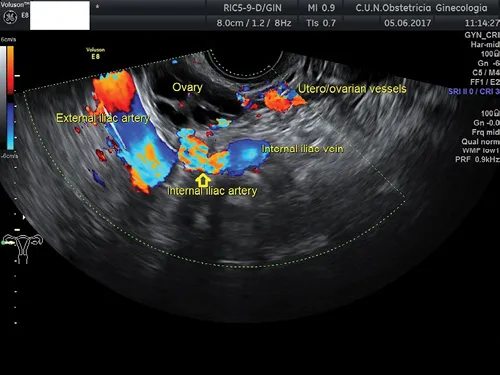

The internal iliac vessels are visible displacing the probe medially and posteriorly (Figure 1.2). Color Doppler may help in identifying these vessels.

Figure 1.2 Transvaginal ultrasound depicting internal iliac vessels and utero-ovarian vessels.